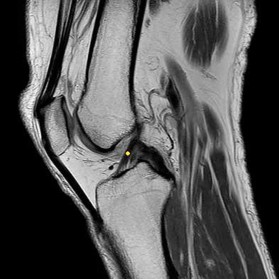

Question 15:

Following a traumatic knee injury, a 24-year-old athlete undergoes an arthroscopic meniscal repair. Which zone of the meniscus has the highest healing potential, and from which vessels does it derive its primary blood supply?

Options:

- Red-red zone; middle geniculate artery

- Red-red zone; medial and lateral superior/inferior geniculate arteries

- White-white zone; popliteal artery

- Red-white zone; descending genicular artery

- White-white zone; avascular (relies on synovial fluid)

Correct Answer: Red-red zone; medial and lateral superior/inferior geniculate arteries

Explanation:

The peripheral 10% to 30% of the meniscus (the red-red zone) is well-vascularized and thus has the highest healing potential. The blood supply to this peripheral zone is derived from the capsular and synovial branches of the medial and lateral, superior and inferior geniculate arteries. The central white-white zone is avascular and relies on diffusion from synovial fluid, lacking the intrinsic capacity to heal.